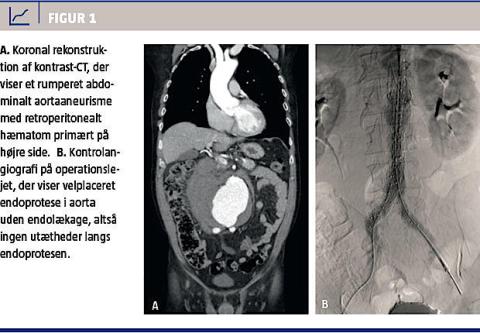

En akut CT med intravenøs kontrast afslørede et 9,4 cm bredt, infrarenalt RAAA (Figur 1A). På baggrund af de anatomiske forhold fandtes det pågældende RAAA egnet til endovaskulær behandling. På en hybridstue (dvs. en operationsstue, hvor der også er mulighed for radiologisk intervention) implanterede man i lokal anæstesi via begge lysker en aorto-biiliakal endoprotese (Figur 1B). Postoperativt kunne patienten mobiliseres efter få timer. Der var normal fodpuls bilateralt og ingen tegn på hæmatomer i

lyskerne, intraabdominalt kompartment, nyrepåvirkning eller tarmiskæmi. Det primære indlæggelsesforløb varede ni dage og var forlænget på grund af intravenøs antibiotisk behandling for pneumoni. Tre dage efter udskrivelsen blev patienten genindlagt pga. trombosering af venstre endoproteseben, der ikke kunne genåbnes, og der blev derfor anlagt en crossover-bypass fra højre a. femoralis til venstre a. fe-

moralis. Patienten måtte i efterforløbet yderligere trombektomeres to gange i hhv. crossover-protesen

og afløbskarrene til venstre ben. Efter yderligere ti dages indlæggelse kunne han udskrives uden varige men. En kontrol-CT tre måneder postoperativt viste tilfredsstillende placering af endoprotesen og reduktion af aneurismediameteren til 7,5 cm. Der var ingen endolækage